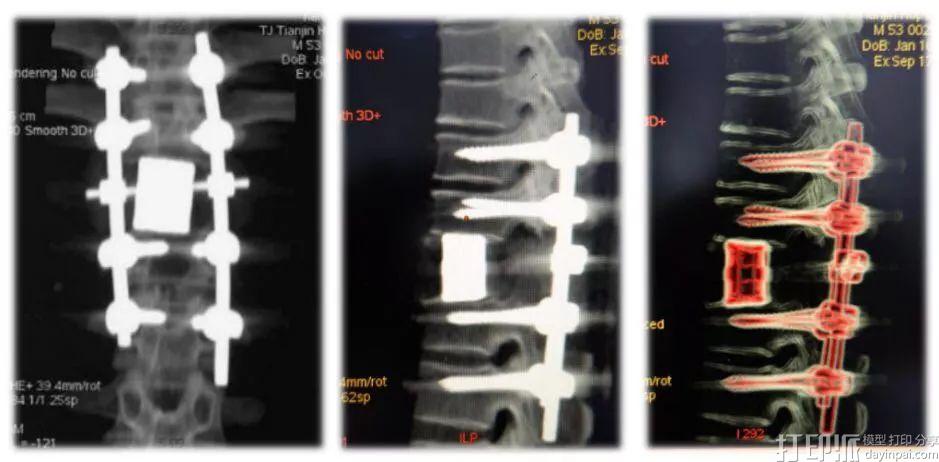

患者术后三维CT重建,可见3D打印人工椎体与上下终板完全重合